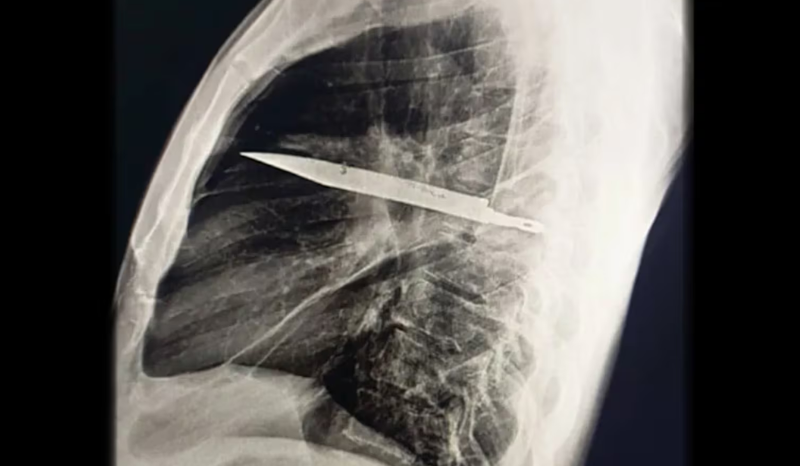

Um homem de 44 anos, da Tanzânia, descobriu que carregava uma lâmina de faca em seu peito há oito anos. O objeto foi identificado após ele procurar atendimento médico devido a secreção no peito. Exames revelaram que a lâmina estava entre as costelas, sem atingir órgãos vitais.

Exames de raio-X revelaram que o corpo do paciente havia formado uma cápsula fibrosa ao redor da lâmina, o que isolou o objeto e evitou danos maiores. Após a descoberta, o paciente foi submetido a uma cirurgia para remoção da lâmina e drenagem da secreção.